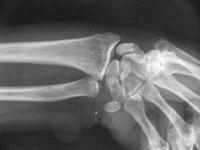

Case 4. Preop dynamic instability

In this case, the scapholunate repair was stabilized with absorbable (Bionx) screws. Provisional fixation for two screws with a pin and a drill.

Click for larger image

These were then replaced with screws, which are radiolucent.

Lucency where a screw lies.

Unfortunately, the screws did not provide adequate stability and lost purchase about six weeks postoperatively. Symptoms remained improved despite early radiographic recurrence of scapholunate diastasis.